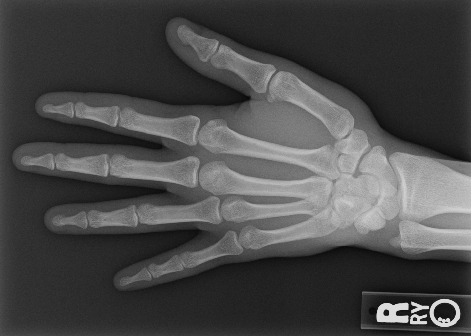

We performed three experiments for our method. First, we perform our method on several X-ray images, showing our method is not restricted by specific imaging objects. Second, we compared our method with image enhancement method and dehazing method, showing that our modification of the original dehazing indeed helps in this task. Third, we perform our method on a hand X-ray image dataset, showing its effectiveness and efficiency.

Several results from our method are shown in Fig. 7. The left column is the original input image. The right two columns are the soft tissue and bone image, respectively. It can be told that the soft tissue image is smooth as we assumed. Meanwhile, the bone image has better image contrast as desired. Moreover, our method can reach real-time performance on these X-ray images. The running time of our method on these images is reported in Table I.

In the third experiment, we applied our method on a hand X-ray image data set (RSNA), which contains more than 10,000 hand X-ray images. And the image has high resolution (usually larger than 1514×2044151420441514\times 2044). These images are collected from clinical applications. Therefore, we can apply our method on these practical images, showing the efficiency and effectiveness of our method on real high resolution images.

In each panel of Fig. 10, the input image (left) is decomposed into soft tissue (middle) and bone image (right) by our method. Although we only show the first ten images from the data set, the results for the rest images are similar.

The bone images have better image contrast since the parameter α1𝛼1\alpha\geq 1 is theoretically guaranteed. Such enhancement can also be directly told by radiologists. Such enhancement is good for bone diagnosis in practical applications.

Moreover, the running time of our method on such high resolution images is less than half second in the MATLAB language on a laptop. Therefore, it can achieve higher performance on a better hardware in real applications. If higher performance is required, our model can be solved by the parallel Laplace equation solver on a modern graphic process unit (GPU), which usually has thousands of cores.